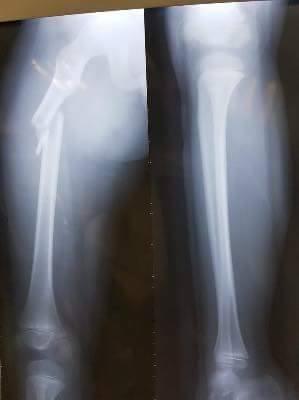

Ảnh chụp X -quang xương chân bị gãy của học sinh Trần Chí Kiên.